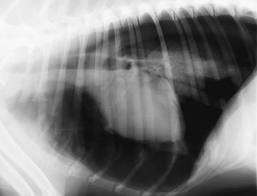

Pneumothorax refers to the accumulation of air with the pleural space.

Fill the pleural space with air and the negative pressure is disrupted resulting in more effort required for lung expansion.

![]()  |

| Pneumothorax |

Pneumothorax  Murphy and Ruska were referred to me to figure out why they had leaky lung lobes.